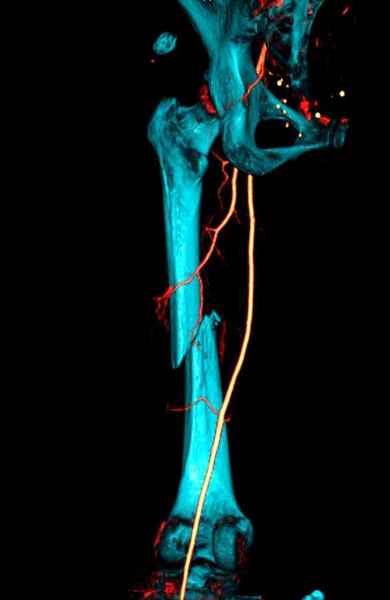

Со слов, больная ничем не болела, только последние 3 месяцев чувствовала боли в бедренной области. КТ брюшной полости подтвердил увеличенную правую почку. (5-6)

Для предупреждения кровотечения во время рассверливания, за день до операции провели эмболизацию сосудов питающий метастаз. http://radiology.rsnajnls.org/cgi/reprint/150/3/673.pdf (7-11, 12-15-16)